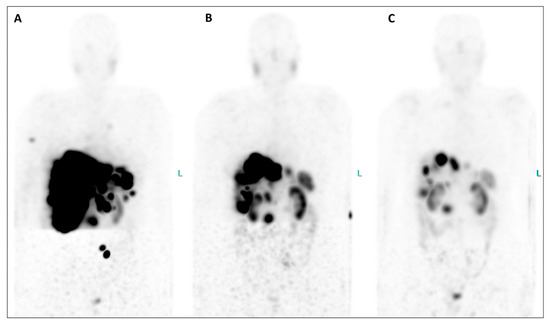

Figure 1. In July 2023, the patient underwent restaging PET/CT with the SSTR antagonist [68Ga]GaDOTA-LM3 ((A), maximum-intensity projection—MIP), revealing an extensive disease burden. Intense uptake of the SSTR antagonist was observed in the pancreatic head, multiple confluent foci in both liver lobes, presenting in a disseminated pattern alongside hepatomegaly and in mediastinal/hilar lymph nodes (Figure 1). Additionally, uptake was noted in several bone segments (right humerus, right scapula, some vertebral bodies, left ilium). Consequently, PRRT with the antagonistic peptide DOTA-LM3 (intravenously administered) was scheduled, involving both beta-emitting Lutetium-177 and alpha-emitting Actinium-225 as 177Lu/225AcDOTA-LM3 (TANDEM-PRRT). The patient underwent three courses of TANDEM-PRRT (July, September, and November 2023), with a total administered activity of 11.3 GBq for [177Lu]LuDOTA-LM3 and 26.4 MBq for [225Ac]AcDOTA-LM3. Therapy was well tolerated without significant acute adverse effects. MIP images from [68Ga]GaDOTA-LM3 PET/CT before the first (A) and second (B) course of TANDEM-PRRT are shown. Comparison of PET/CT after a single course of TANDEM therapy with the antagonist DOTA-LM3 showed an excellent response. Liver metastases and the primary pancreatic tumor exhibited extraordinary improvement, accompanied by a marked reduction in liver size. No significant DOTA-LM3 uptake was detected in the mediastinal/hilar lymph nodal metastases and most bone lesions, with only faint residual uptake in the left pelvis metastasis. Notably, no new distant metastases were detected.